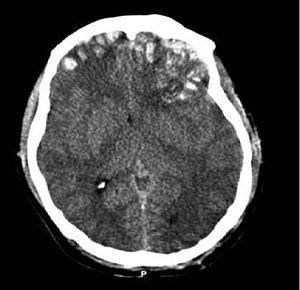

Brain trauma CT.jpg

CT scan showing cerebral contusions, hemorrhage within the hemispheres, subdural hematoma, and skull fractures[2]